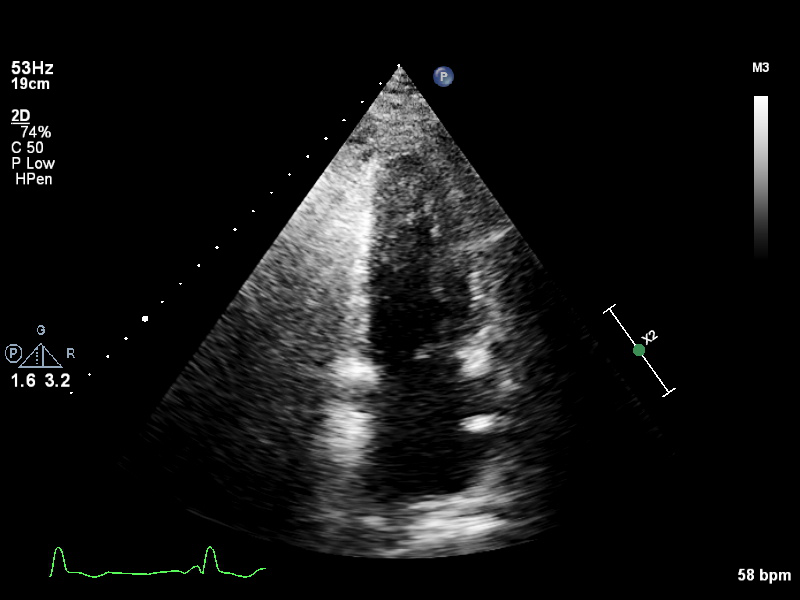

ImageView NameDescription

a4ch-full a4ch-full Apical 4-chamber showing the full depth of all four chambers (no LV/RV focus)

a4ch-ias a4ch-ias Apical 4-chamber, focused on the inter-atrial septum

a4ch-la a4ch-la A4CH with Doppler near MV/LA or 2D covering full LA, not full LV

a4ch-lv a4ch-lv A4CH covering the whole depth of the LV, not the whole depth of the LA

a4ch-ra a4ch-ra Apical 4-chamber focused on the right atrium, or colour Doppler on TV/RA

a4ch-rv a4ch-rv Apical 4-chamber focused on the right ventricle